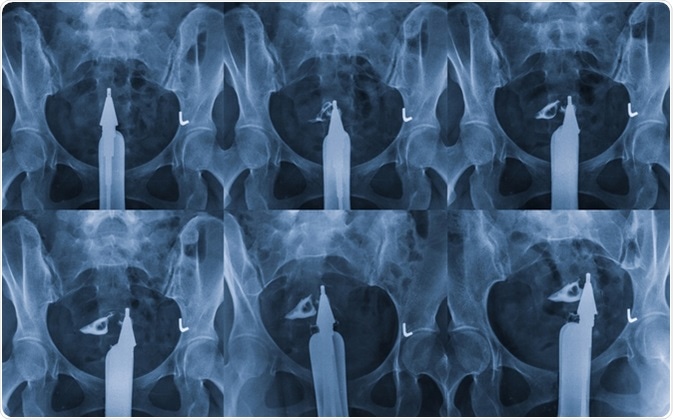

Hysterosalpingography is a type of X-ray called fluoroscopy that looks at a woman

Hysterosalpingography is a type of X-ray called fluoroscopy that looks at a woman's uterus and fallopian tubes. Image Credit: MossStudio / Shutterstock